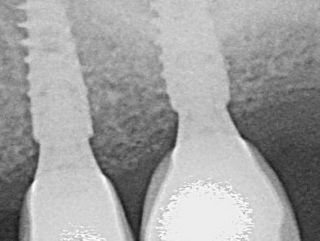

Dr. Jean-Baptiste VERDINO, France In this clinical case, the use of Axiom X3® TL implants was an asset on several levels. The design of the coils enabled primary stability of 35 N.cm... Read more